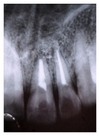

A 25-year-old female reported to the Department of Conservative Dentistry and Endodontics with chief complaint of swelling and pus discharge from upper front tooth region since 1 month. Past dental history revealed trauma which she sustained 8 yrs back in the same region. On intraoral examination, there was a draining sinus, in relation to the apex of 21. On Electric pulp testing, tooth number 22 was also found nonvital. Periapical radiograph revealed a large diffused periapical radiolucency in relation to 21 and 22 measuring 1.4 cm in diameter (Figure 1).

In the present case, it was observed that at 3- (Figure 6), 6- (Figure 7), 9- (Figure 8), and 12- (Figure 9) month followup after the surgical treatment of large chronic periapical lesion, PRF combined with beta-tricalcium resulted in significant, progressive, and predictable clinical and radiographic bone regeneration.